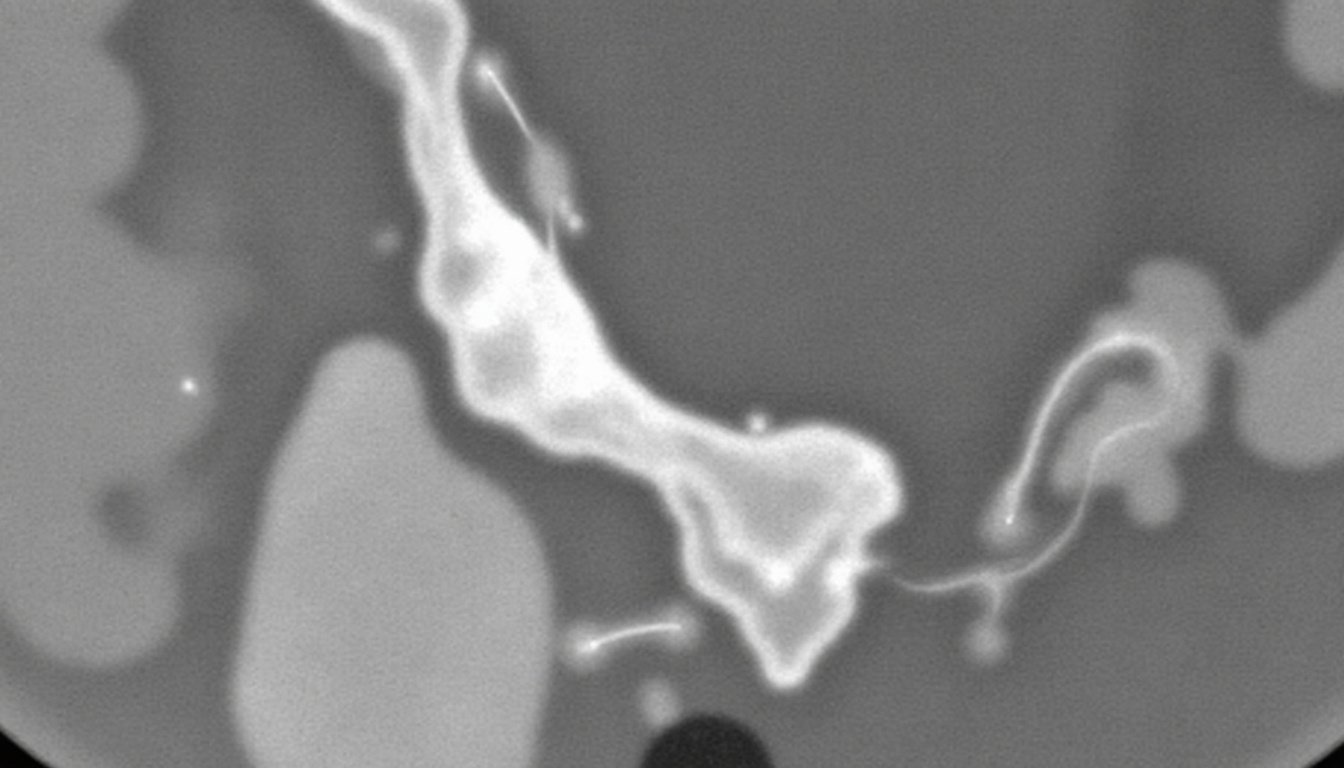

En cas d’inflammation sévère, un médecin pourra recourir à une échographie pour visualiser tendons et muscles, notamment dans les cas évoqués par La Clinique du Coureur, afin de confirmer la nature de la blessure.